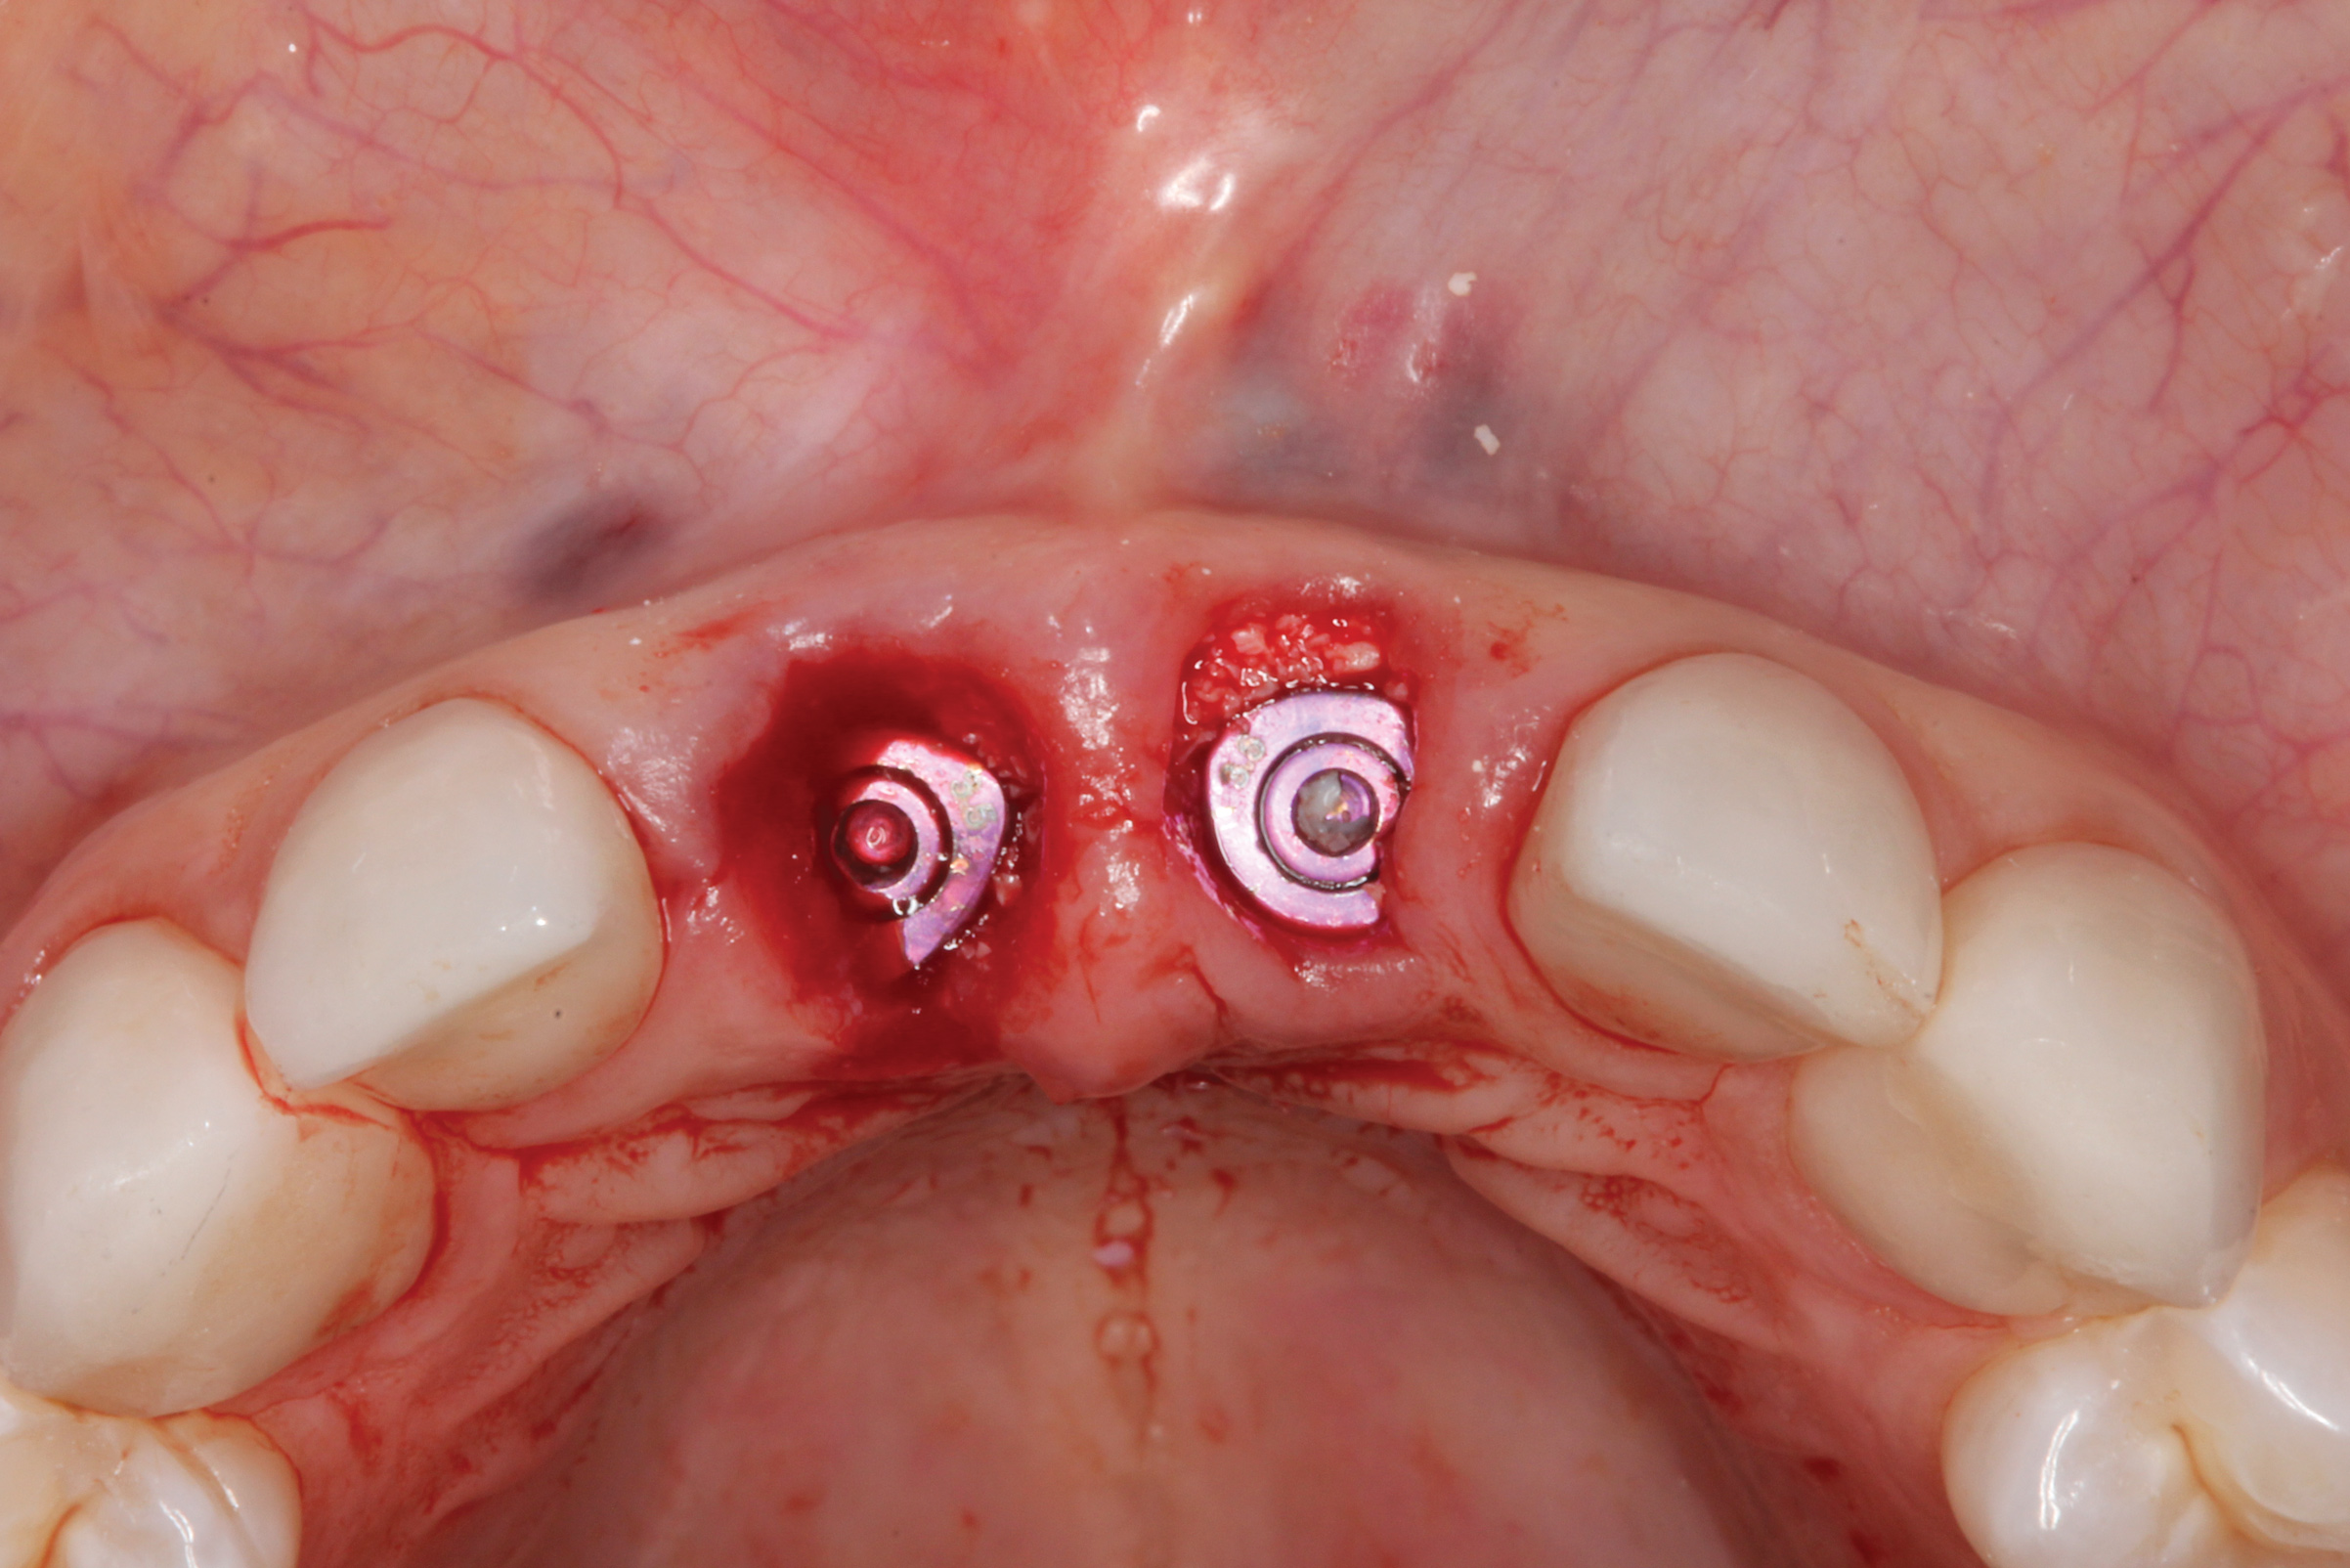

The surgery was performed under local-regional anesthesia. The thermoplastic retainer was placed over the remaining teeth and its fit/stability verified. Atraumatic extractions of teeth Nos. 8 and 9 were performed, and intact buccal bone was verified. Osteotomy site preparation and immediate implant placement were performed using the dynamic surgical navigation system. Two 3.6 mm x 9 mm implant fixtures (Astra Tech EV, Dentsply Sirona, dentsplysirona.com) were placed. SmartPegs (Osstell, osstell.com) were attached to the implants to show the trajectory of the fixture positioning. After implant placement, anorganic bovine bone matrix (Bio-Oss®, Geistlich Pharma, geistlich-na.com) was used to graft the implant alveolus "gap," and healing abutments were placed (Figure 9 and Figure 10). The patient was provided with an interim removable appliance for tooth replacement.

Fig 10. Healing abutments were placed, and implant/alveoli gaps were managed with placement of anorganic bovine bone.

Figure 10